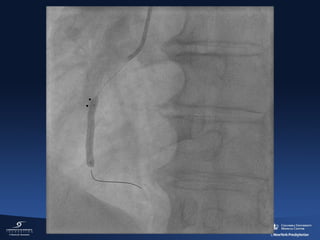

Case 1

Clinical presentation

• 55 yo M

• No prior medical history

• No family history of premature CAD

• New onset chest pain at rest (1 AM)

• Emergency room 30 min after chest

pain

• STEMI inferior wall with complete AV

block; ventricular rhythm 35 bpm

ASA 320 mg

Ticagrelor

180mg

Heparin 5,000 U

Bivalirudin

BP 80/50 mmhg

Pacemaker RFV

1 liter of fluid

2 thrombo-aspiration runs large

thrombus removed

Post Thrombo-aspiration

ER to TIMI 3